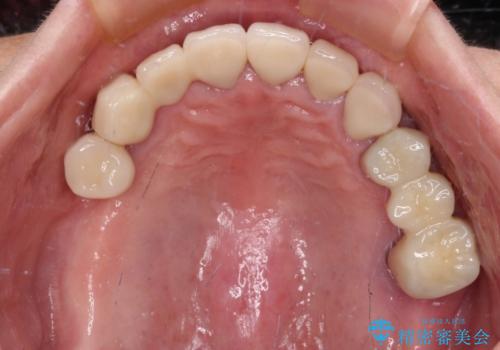

前歯部については抜歯が必要な歯を抜歯し、インプラントやブリッジなどにより補綴治療を行うこととしました。

臼歯部は今後抜歯が必要となった際に、インプラントにより咬合を構築していくこととしました。今回の治療においても、今後の臼歯部の治療に対応できるよう治療計画を立案しています。